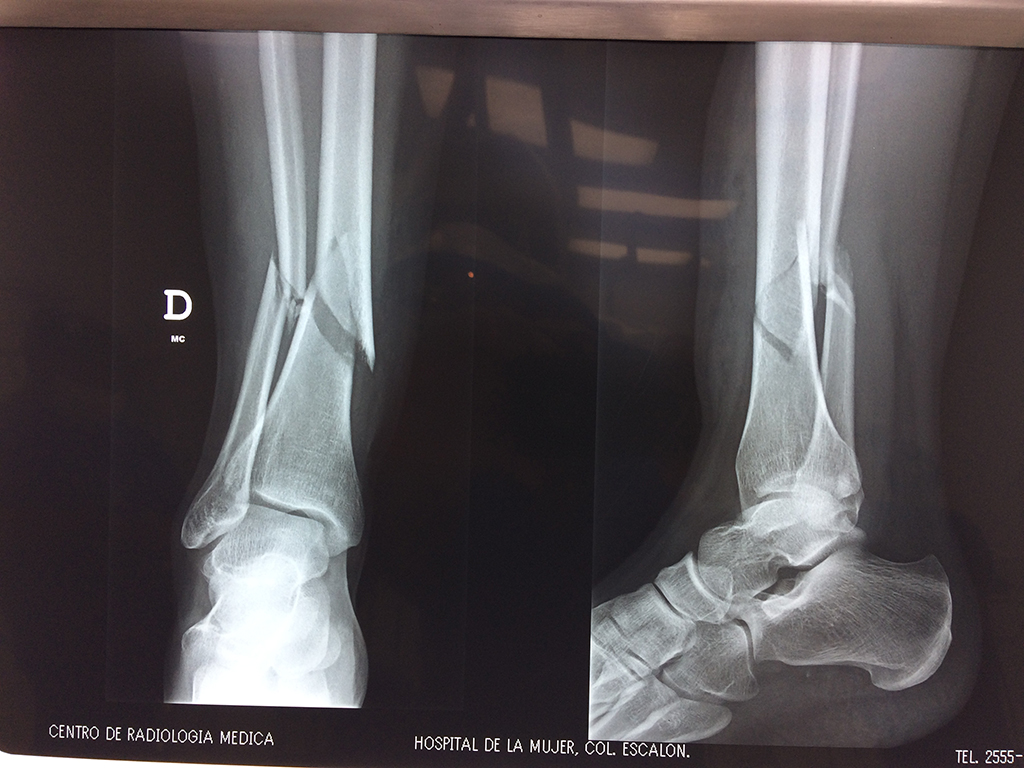

Cirugía de Tibia y Peroné

Aunque cada uno de estos huesos puede fracturarse por separado, normalmente la rotura es una lesión que se produce de forma conjunta

La mayor parte de las roturas implican a la parte proximal del hueso (parte del hueso próximo a la rodilla) o a la parte distal (parte del hueso cerca del tobillo).

Debido a la fina cobertura de piel que recubre la tibia y el peroné, las fracturas generalmente son abiertas, es decir, el hueso roto rasga la piel, atravesándola. Las fracturas de tibia y peroné generalmente se producen por un fuerte impacto o torsión.